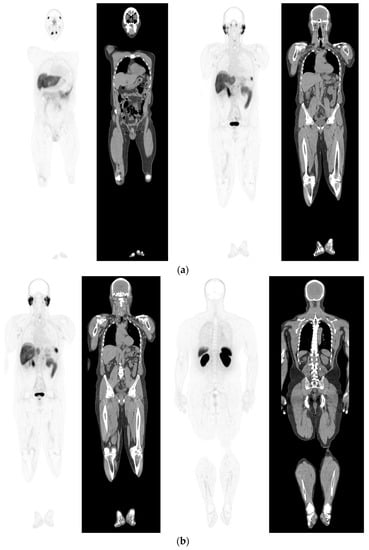

To date there have been multiple meta-analyses assessing the utility of PSMA PET-CT [108,109,110,111,112,113] to detect recurrence. In patients with BCR, the proportion of positive PSMA PET-CT scans consistently increased with higher PSA. For PSA categories 0–0.19, 0.2–0.49, 0.5–0.99, 1–1.99, and >2 ng/mL, the percentages of positive scans were 33%, 45%, 59%, 75%, and 95%, respectively. Significantly, PSMA PET-CT improves the detection of recurrence at low PSA (<0.5 ng/mL), and has high sensitivity (75%) and specificity (99%) on meta-analysis of pooled data (Figure 4) [108]. Furthermore, a meta-analysis by Kimura et al., (2020) looking at accuracy for PSMA PET-CT performed prior to salvage lymph node dissection for nodal recurrence in PCa patients with BCR (462 patients, 14 studies) found sensitivity using lesion based analysis of 0.84 (95%CI: 0.61–0.95) and specificity 0.97 (95% CI: 0.95–0.99) [113].

Figure 4.

Biochemical recurrence—serial scans. 58 yr old M—radical prostatectomy and node disSection 10 yrs prior; scans done in July 2020 when PSA 0.24 and Sep 2021 when PSA 0.38. (a): PSMA PET-CT: July 2020-68Ga-PSMA-226 MBq; uptake 49 min; BMI = 35.1; Wt 105 kg; coronal images and transaxial images at level of prostate bed show tracer excretion; rest of study clear. (b): PSMA PET-CT: Sep 2021-68Ga-PSMA-238 MBq; uptake 50 min; BMI = 35.2; Wt 107 kg; coronal images and transaxial images at level of prostate bed show tracer excretion but with a new small focus of uptake SUV= 6.0 in left side of prostate bed; rest of study clear.